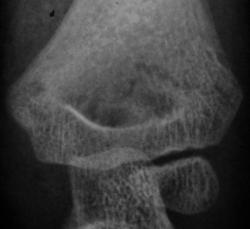

Пол пациента: Мужской пол Тип патологии: Травма Область исследования: Скелетно-мышечная система Методы исследования: Rg Рентгенограммы произведены в "ургентном" порядке ургентным лаборантом. Пациент направлен на исследование дежулным хирургом. ВАШЕ МНЕНИЕ КОЛЛЕГИ? TRAVMA.1..JPG TRAVMA_2..jpg TRAVMA.3..jpg TRAVMA.4..JPG TRAVMA.5..JPG AttachmentSize TRAVMA.1..JPG45.46 KB TRAVMA_2..jpg78.72 KB TRAVMA.3..jpg82 KB TRAVMA.4..JPG57.79 KB TRAVMA.5..JPG76.83 KB Mon, 16/11/2009 - 18:06 #1 v1tal Offline Last seen: 4 years 10 months ago Joined: 07.06.2008 - 19:41 Posts: 1779 Супракондилярный перелом дистального эпифиза плечевой кости, с незначительным угловым смещением открытым кзади. "Знаешь, у некоторых врачей есть комплекс мессии — им необходимо спасать мир. А у тебя комплекс Рубика — тебе необходимо решать головоломки." Mon, 16/11/2009 - 22:39 #2 В.Б. Серов Offline Last seen: 3 weeks 6 days ago Joined: 16.07.2008 - 10:15 Posts: 1361 Перелом вижу, смещения - нет Зри в корень! Mon, 16/11/2009 - 23:06 #3 Анатолий Владим... Offline Last seen: 7 years 10 months ago Joined: 16.10.2009 - 21:16 Posts: 1941 А смещение действительно минимальное.

Супракондилярный перелом дистального эпифиза плечевой кости, с незначительным угловым смещением открытым кзади.

Перелом вижу, смещения - нет

А смещение действительно минимальное.